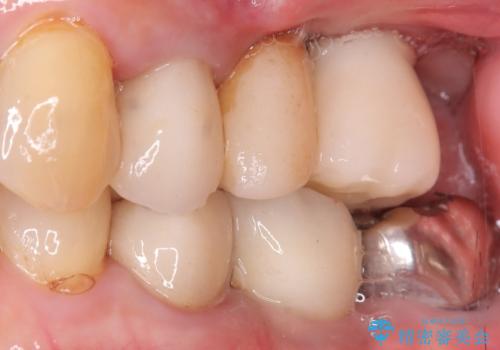

- 主訴:食べ物噛むと左奥歯が痛い

左上6番目の歯が根っこ部分で破折しており、噛むたびに痛みが生じる状態でした。

保存不可能と判断し、抜歯から骨ができるのを3か月待ってインプラント治療を行いました。

歯根破折により抜歯となり、インプラント治療(一回法)にて補綴修復を行いました。

抜歯から3か月程骨ができてくるのを待ってからインプラントを埋入しています。